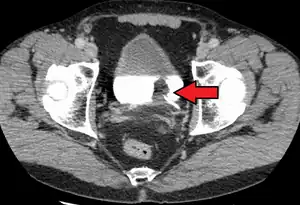

Diagnosis

Bladder tumor in FDG PET due to the high physiological FDG-concentration in the bladder, furosemide was supplied together with 200 MBq FDG. The uptake cranial to the lesion is a physiological uptake in the colon.

If invasive or high grade (includes carcinoma in situ) cancer is detected on TURBT, an MRI and/or CT scan of the abdomen and pelvis or urogram and CT chest or x-ray chest should be conducted for disease staging and to look for cancer spread (metastasis). Increase in alkaline phosphatase levels without evidence of liver disease should be evaluated for bone metastasis by a bone scan.[1] Although 18F-fluorodeoxyglucose (FDG)-positron emission tomography (PET)/CT has been explored as a viable method for staging, there is no consensus to support its role in routine clinical evaluations.[54]